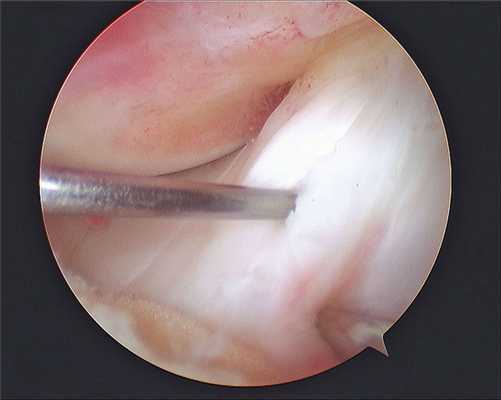

Изображение полости сустава.

В целях высокоинформативной диагностики специалист через микропортал вводит рабочую трубку устройства внутрь сустава, в которую вмонтированы система ультрасильных линз, мощный световой источник и видеозаписывающая цифровая техника. Все структуры, что «видит» артроскоп, визуализируются на экране в «живом» виде, причем изображение поступает в многократно увеличенном формате. Врач может найти точное расположение травмы или дегенеративных изменений, установить характер патологии, степень тяжести и принять меры.

Сначала, вне зависимости от планов хирурга, будет осуществлена диагностическая артроскопия. Она предусматривает введение эндоскопического зонда в виде стержня в полость костного соединения. Когда наркоз вступит в силу, тогда начинается диагност-хирургия. Для этого полусогнутую в колене конечность ближе к бедру жгутируют для уменьшения кровотока, после чего делают прокол (6 мм), через который подается контраст-вещество, чтобы усилить видимость суставных и околосуставных структур. Далее через этот операционный порт вводится трубка. Специалист досконально осматривает каждый миллиметр проблемного органа.

Видео в реальном времени транслируется на экране, выявляет любые существующие дефекты в больном сочленении. Если врач посчитает нужным выполнить регенерацию патологических элементов, он создаст дополнительный разрез (6-8 мм), через который нужным инструментом из микрохирургического набора устранит обнаруженный дефект. Он может сделать частичную резекцию костно-хрящевых тканей, пластику связок и сухожилий, сшивание или удаление (частичное, полное) мениска, экспроприировать хондромные тела, извлечь выпот и гной, ввести противовоспалительные лекарства, взять фрагмент тканей или синовии для изучения их состава и др.